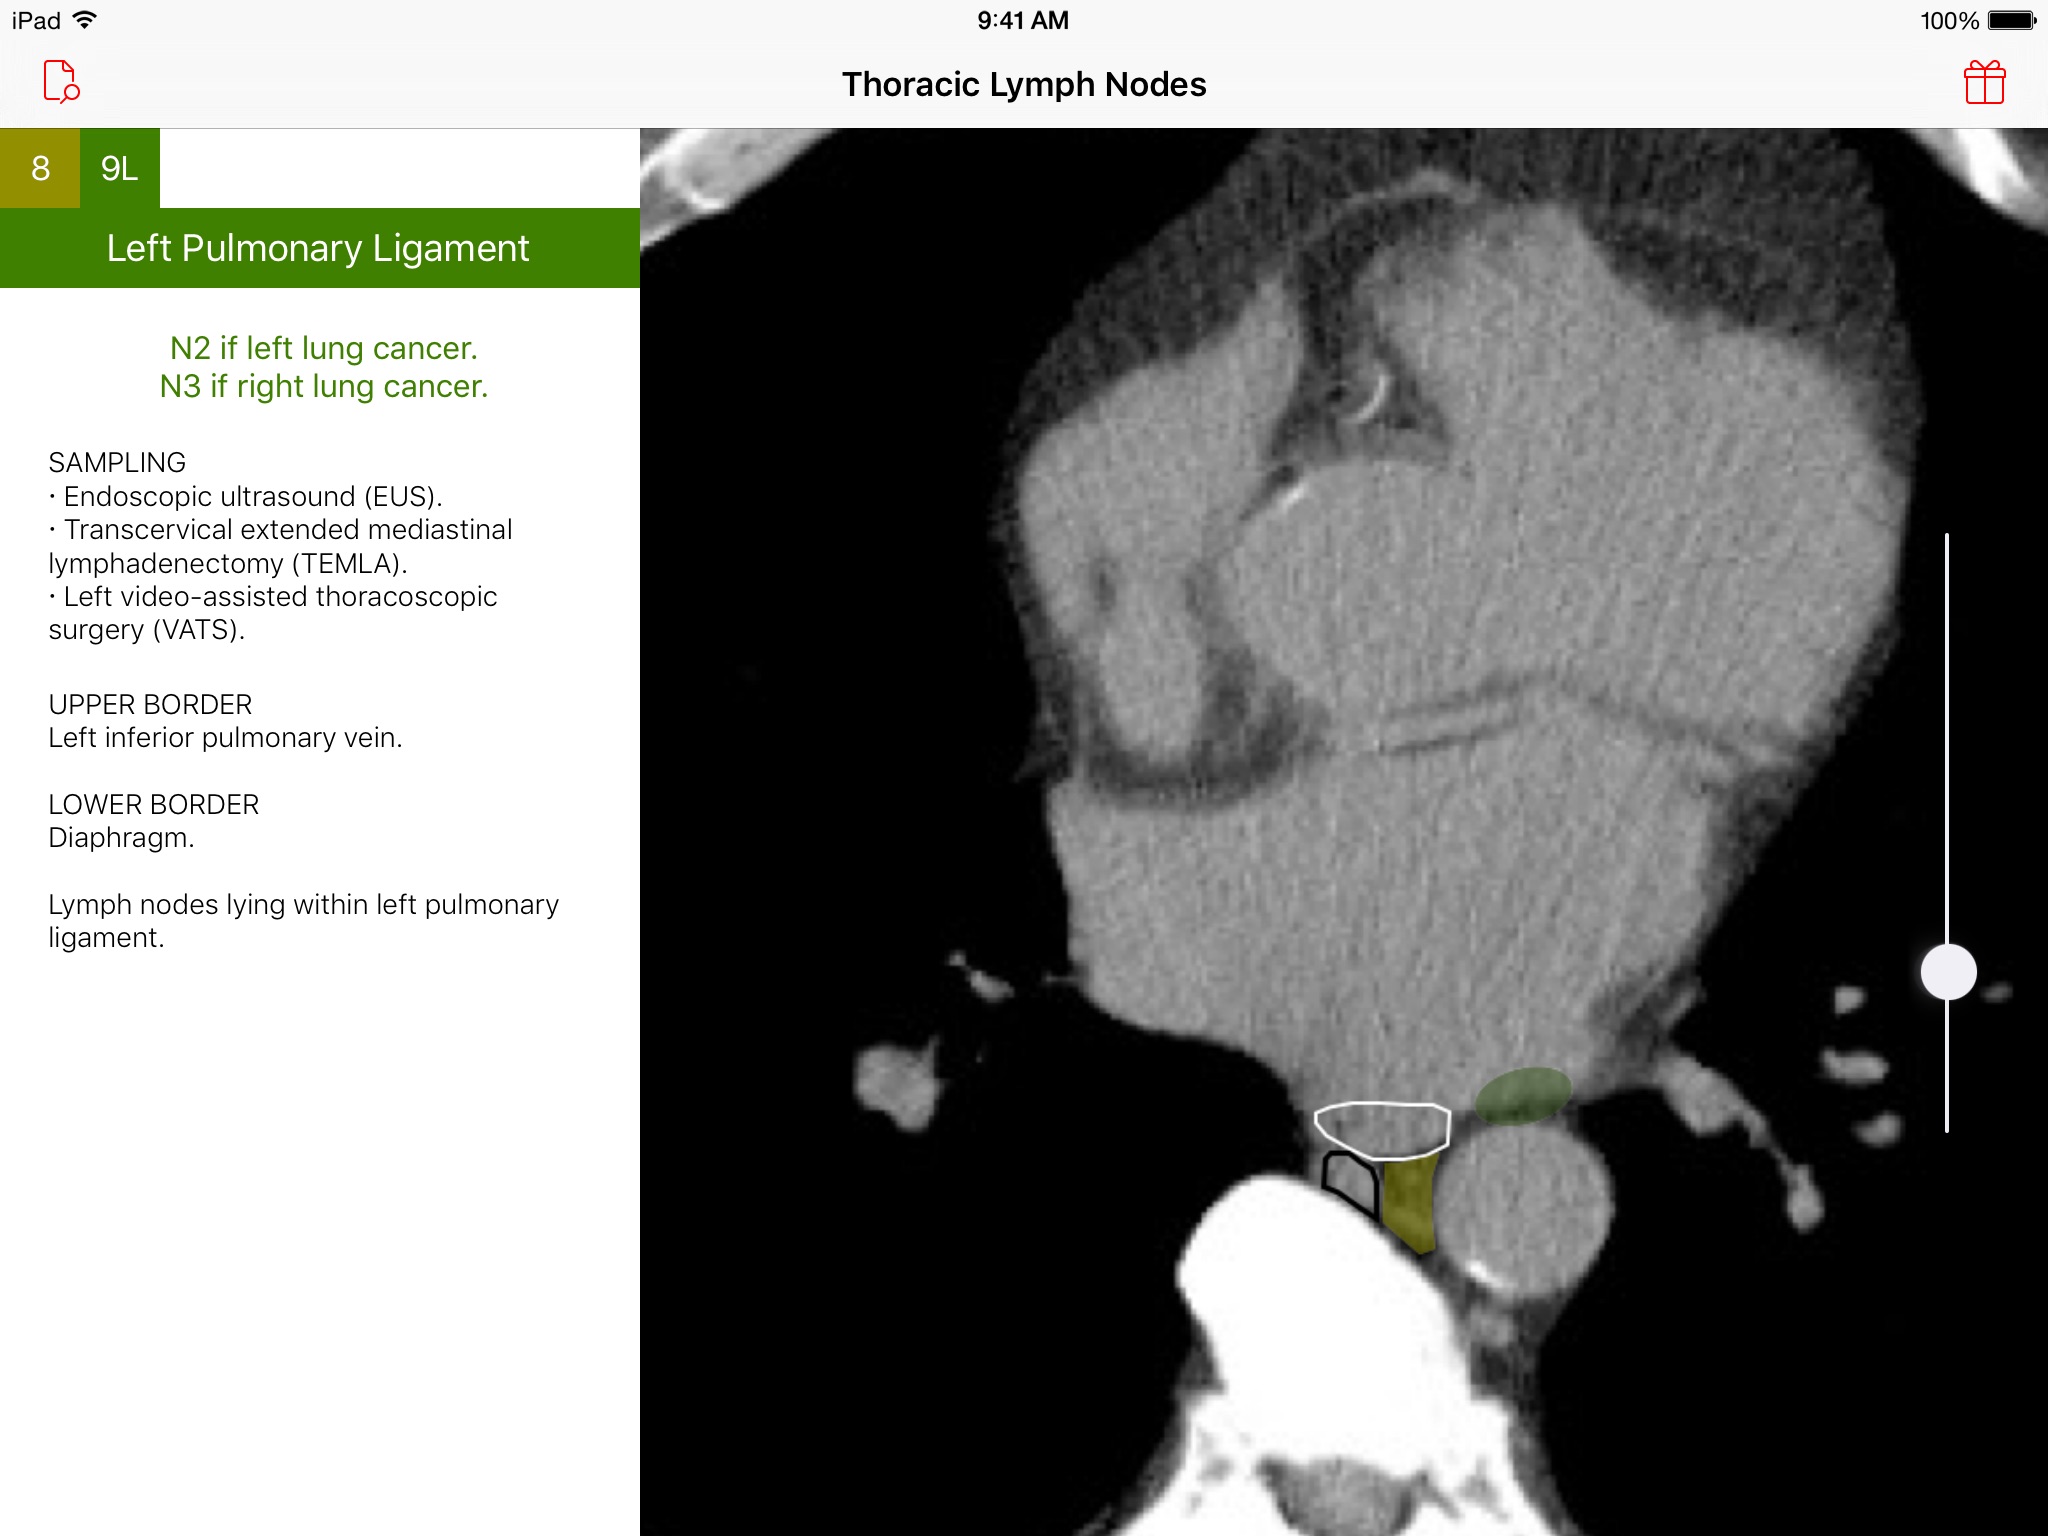

Introducing the Thoracic Lymph Node Map app, an elegant tool that provides healthcare professionals with a color-coded CT lymph node map adapted from the International Association for the Study of Lung Cancer (IASLC) lung cancer project. Effortlessly navigate through CT images of the chest and view beautifully illustrated, color-coded thoracic CT lymph node map anatomic definitions for each lymph node station. Delve deeper and learn more about classification, sampling options, and anatomic details of each lymph node station. Browse · Regional thoracic lymph node station territories · Relationships between different regional lymph node stations within the chest Discover · Clinical regional lymph node classification for each lymph node station · Sampling options for each lymph node station · Anatomic boundaries for each lymph node station Requirements · A device with iOS 8 or later This app was developed as a service to the medical community and is provided free of charge and free of advertising.